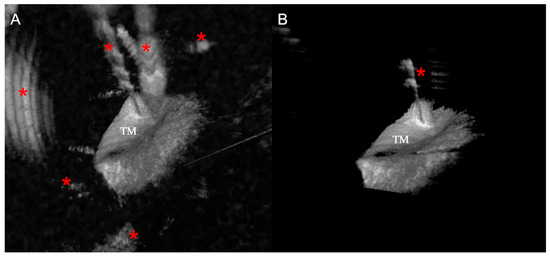

2.5. Image Recognition Algorithms

2.6. 3D Reconstruction Algorithm